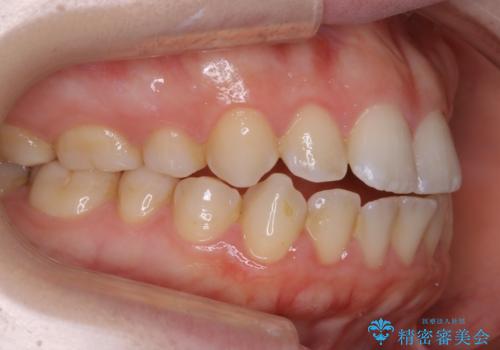

【非抜歯】上下の前歯が噛み合わないオープンバイトの治療

- 噛み合わせの不調を主訴にご来院されました。

骨格的な問題もあり、噛んだ時に奥歯しか当たらず前歯の被蓋があまりない状態でした。

臼歯の位置が高く噛んだ時に奥歯しか当たらなかったり、舌癖などが原因で前歯が前に倒れてしまうことで上下の前歯の被蓋がなくなってしまっている状態をオープンバイトといいます。

前者の場合は臼歯を圧下し沈めてあげることで改善させます。後者の場合は前方に傾斜している歯を元の角度に戻してあげることで改善しますが、舌癖がある場合はその癖自体を無くす治療をしない限りまた同じ状態へと後戻りしてしまいます。